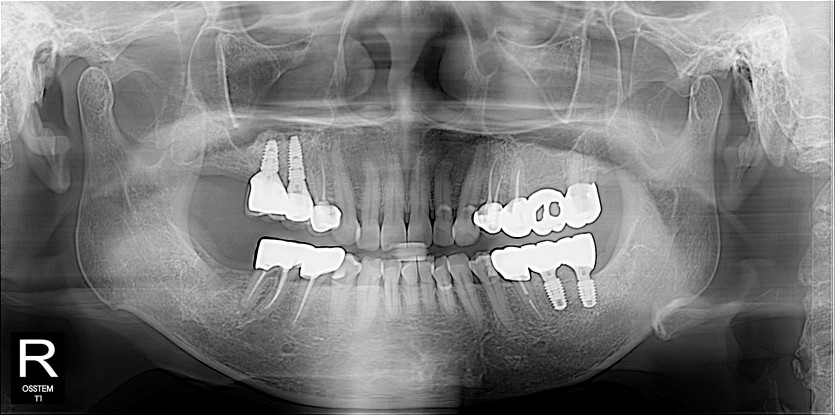

임플란트 사례